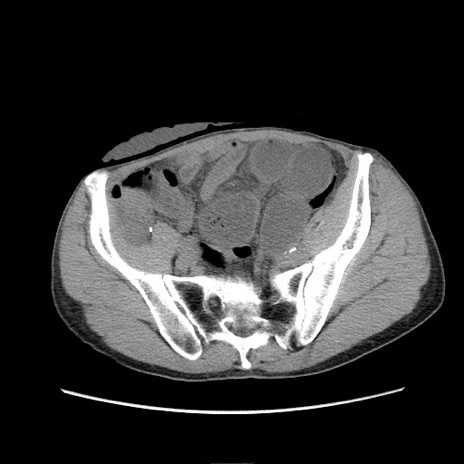

症例11(横断像)

【症例】 60歳代男性

【主訴】 下腹部痛

【現病歴】 本日夜中より下腹部痛の症状認め、受診。

【既往歴】 膀胱癌(膀胱全摘+尿管皮膚瘻術) 、胃癌術後

【身体所見】 BT 35.3℃、PR 58/min、BP 136/98mHg、腹部平坦、軟、腸蠕動音±、ストマ留置あり、左上腹部~正中部に圧痛あり、反跳痛なし。

【データ】WBC 5100、CRP0.01